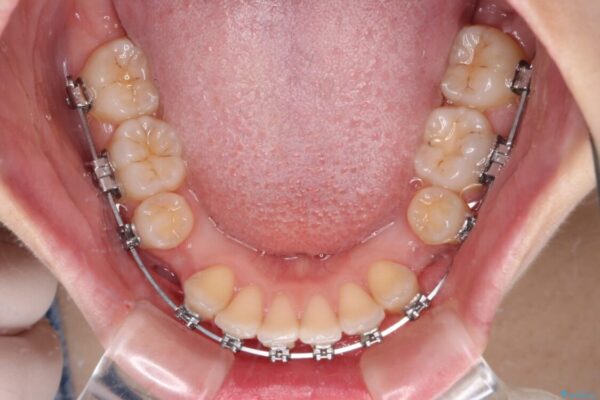

治療途中

• 【モニター】口が閉じられない ワイヤー装置での抜歯矯正 治療途中画像